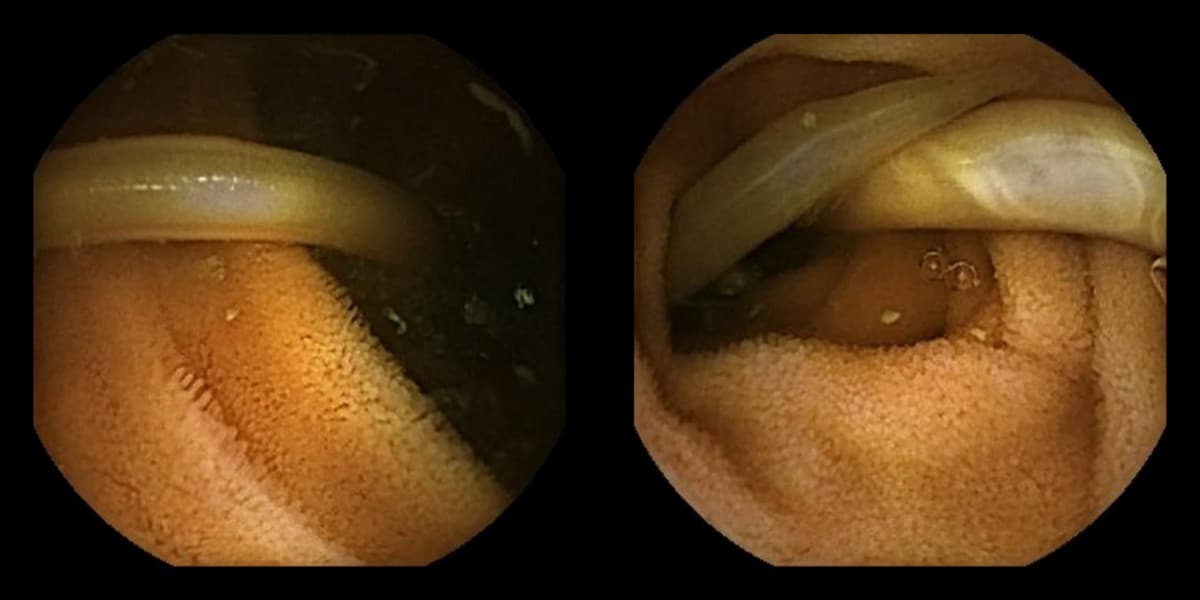

En 48-årig mand med lang rejseanamnese, senest i 2019 til Bali og Kina, blev henvist til endoskopi på grund af episodevis blod per rectum, kvalme, madlede, smerte i epigastriet og et mindre vægttab på ca. 2 kg over få måneder. Det gav ingen forklaring at foretage gastroskopi og koloskopi, og biokemisk registreredes ingen leverpåvirkning samt normale niveauer af amylase, IgE og hæmoglobin. Efterfølgende kapselendoskopi var uden angiodysplasier, men til gengæld påvistes Ascaris proksimalt i jejunum. Patienten blev behandlet med albendazol, og efterfølgende fæcesprøver var uden forekomst af ormeæg.

Ascaris er den største intestinale rundorm, som kan blive op til 35 cm lang. Højeste prævalens findes i Asien, og smitte sker typisk gennem vand eller fødevarer kontamineret med befrugtede æg. Ægget klækkes i tyndtarmen, og larven invaderer tarmmucosa, transporteres til lungerne, ascenderer til øvre luftveje og sluges. Tilbage i tyndtarmen udvikler larven sig til voksenstadiet, og denne cyklus varer typisk 2-3 måneder. Ascariasis kan være asymptomatisk eller præsentere sig som hoste, malnutrition eller obstruktive symptomer fra pancreas og lever-galde-veje. Synlig blødning fra tarmen er en sjælden præsentation ved ormeinfestation [1], hvor kapselendoskopi kan bidrage diagnostisk.